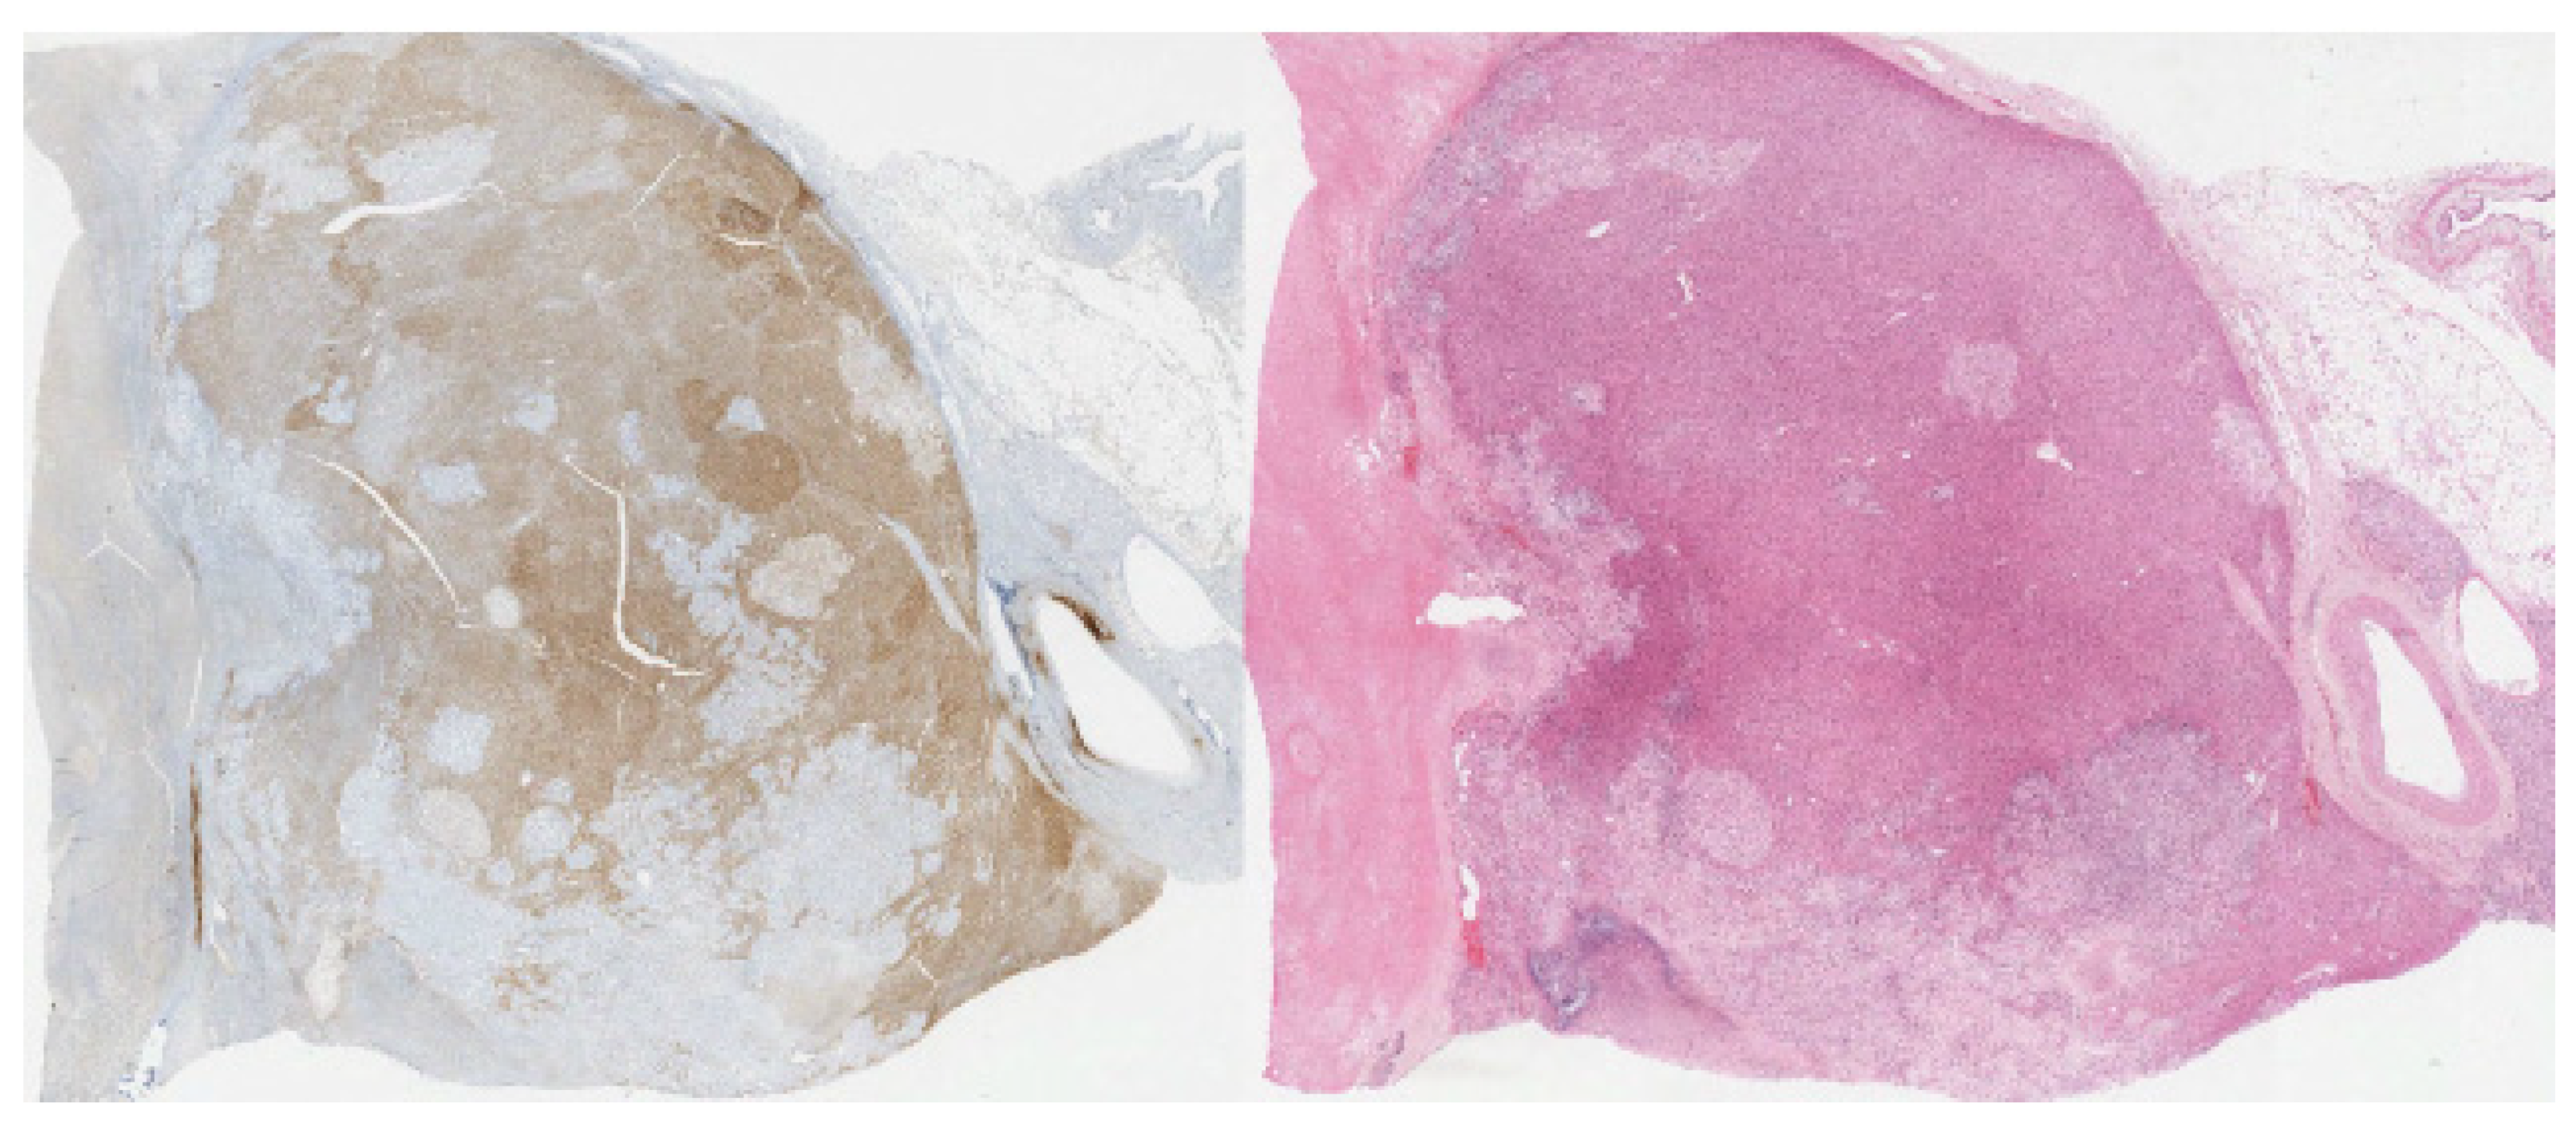

| Stain | Carcinomatous Component | Sarcomatous Component | Company | Clone |

|---|---|---|---|---|

| Calretinin | Positive | Negative | Ventana | SP65 |

| HMB-45 | Negative | Negative | Ventana | HMB-65 |

| Inhibin Alpha | Positive | Negative | Ventana | R1 |

| Synaptophysin | Positive | Negative | Ventana | SP11 |

| Myogenin | Negative | Negative | Ventana | F5D |

| Vimentin | Negative | Positive | Ventana | Vim 3B4 |

| Desmin | Negative | Positive | Ventana | DE-R-11 |

| Pax8 | Negative | Negative | Ventana | MRQ-50 |

| Pan-keratin | Negative | Negative | Ventana | AE1/AE3/PCK 26 |